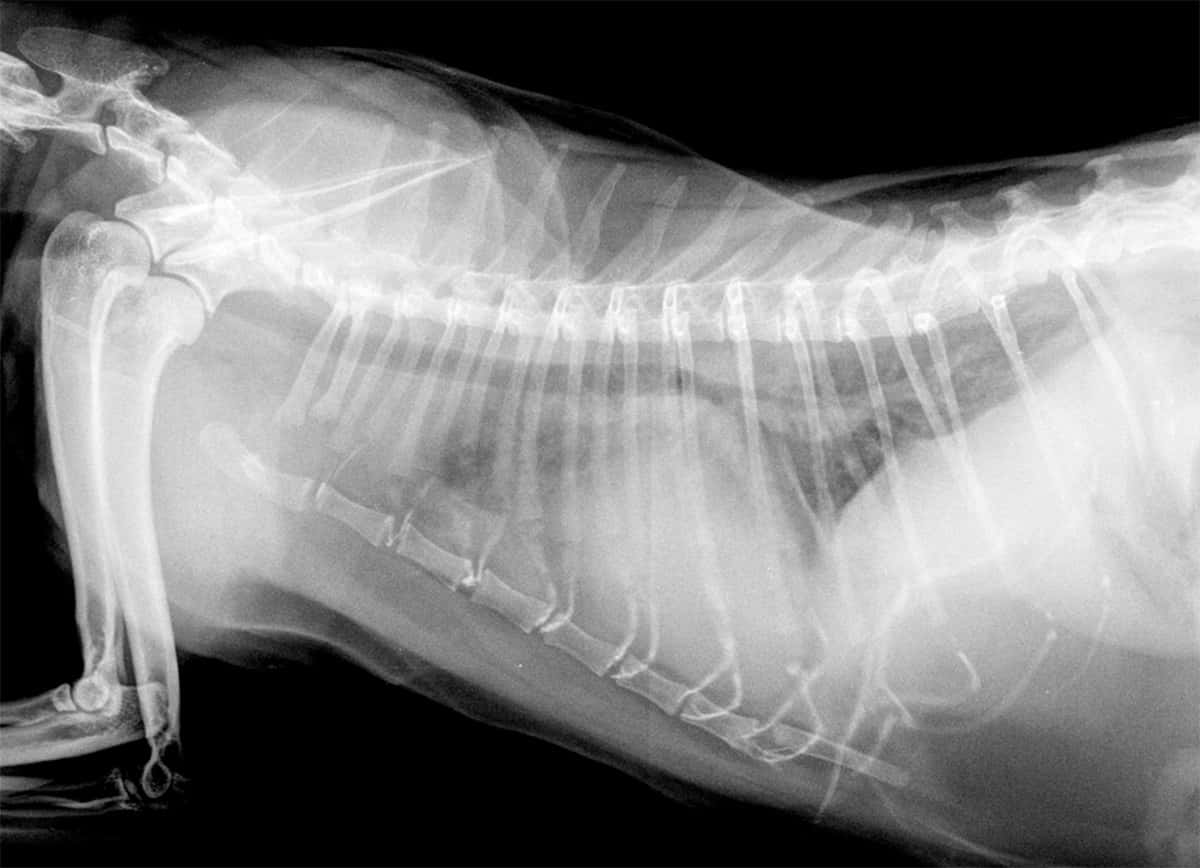

Oedème pulmonaire cardiogénique chez un chat atteint de cardiomyopathie hypertrophique

Nos cliniques sont équipées de système de radiographie numérique. La radiographie est une technique d’imagerie non invasive permettant au moyen de rayons X de visualiser l’intérieur du patient.

Elle demeure une des techniques d’imagerie primaire pour visualiser les différentes parties de l’organisme :

- squelette : mise en évidence de fractures, de luxations, de tumeurs osseuses, de lésions articulaires, recherche de dysplasie, de troubles de croissance…

- examen du thorax : lésions pulmonaires, cardiaques, pleurales, recherche de métastases…

- examen de l’abdomen : recherche de corps étranger, de calculs, d’augmentation de taille d’un organe, de présence de liquide, d’occlusion…